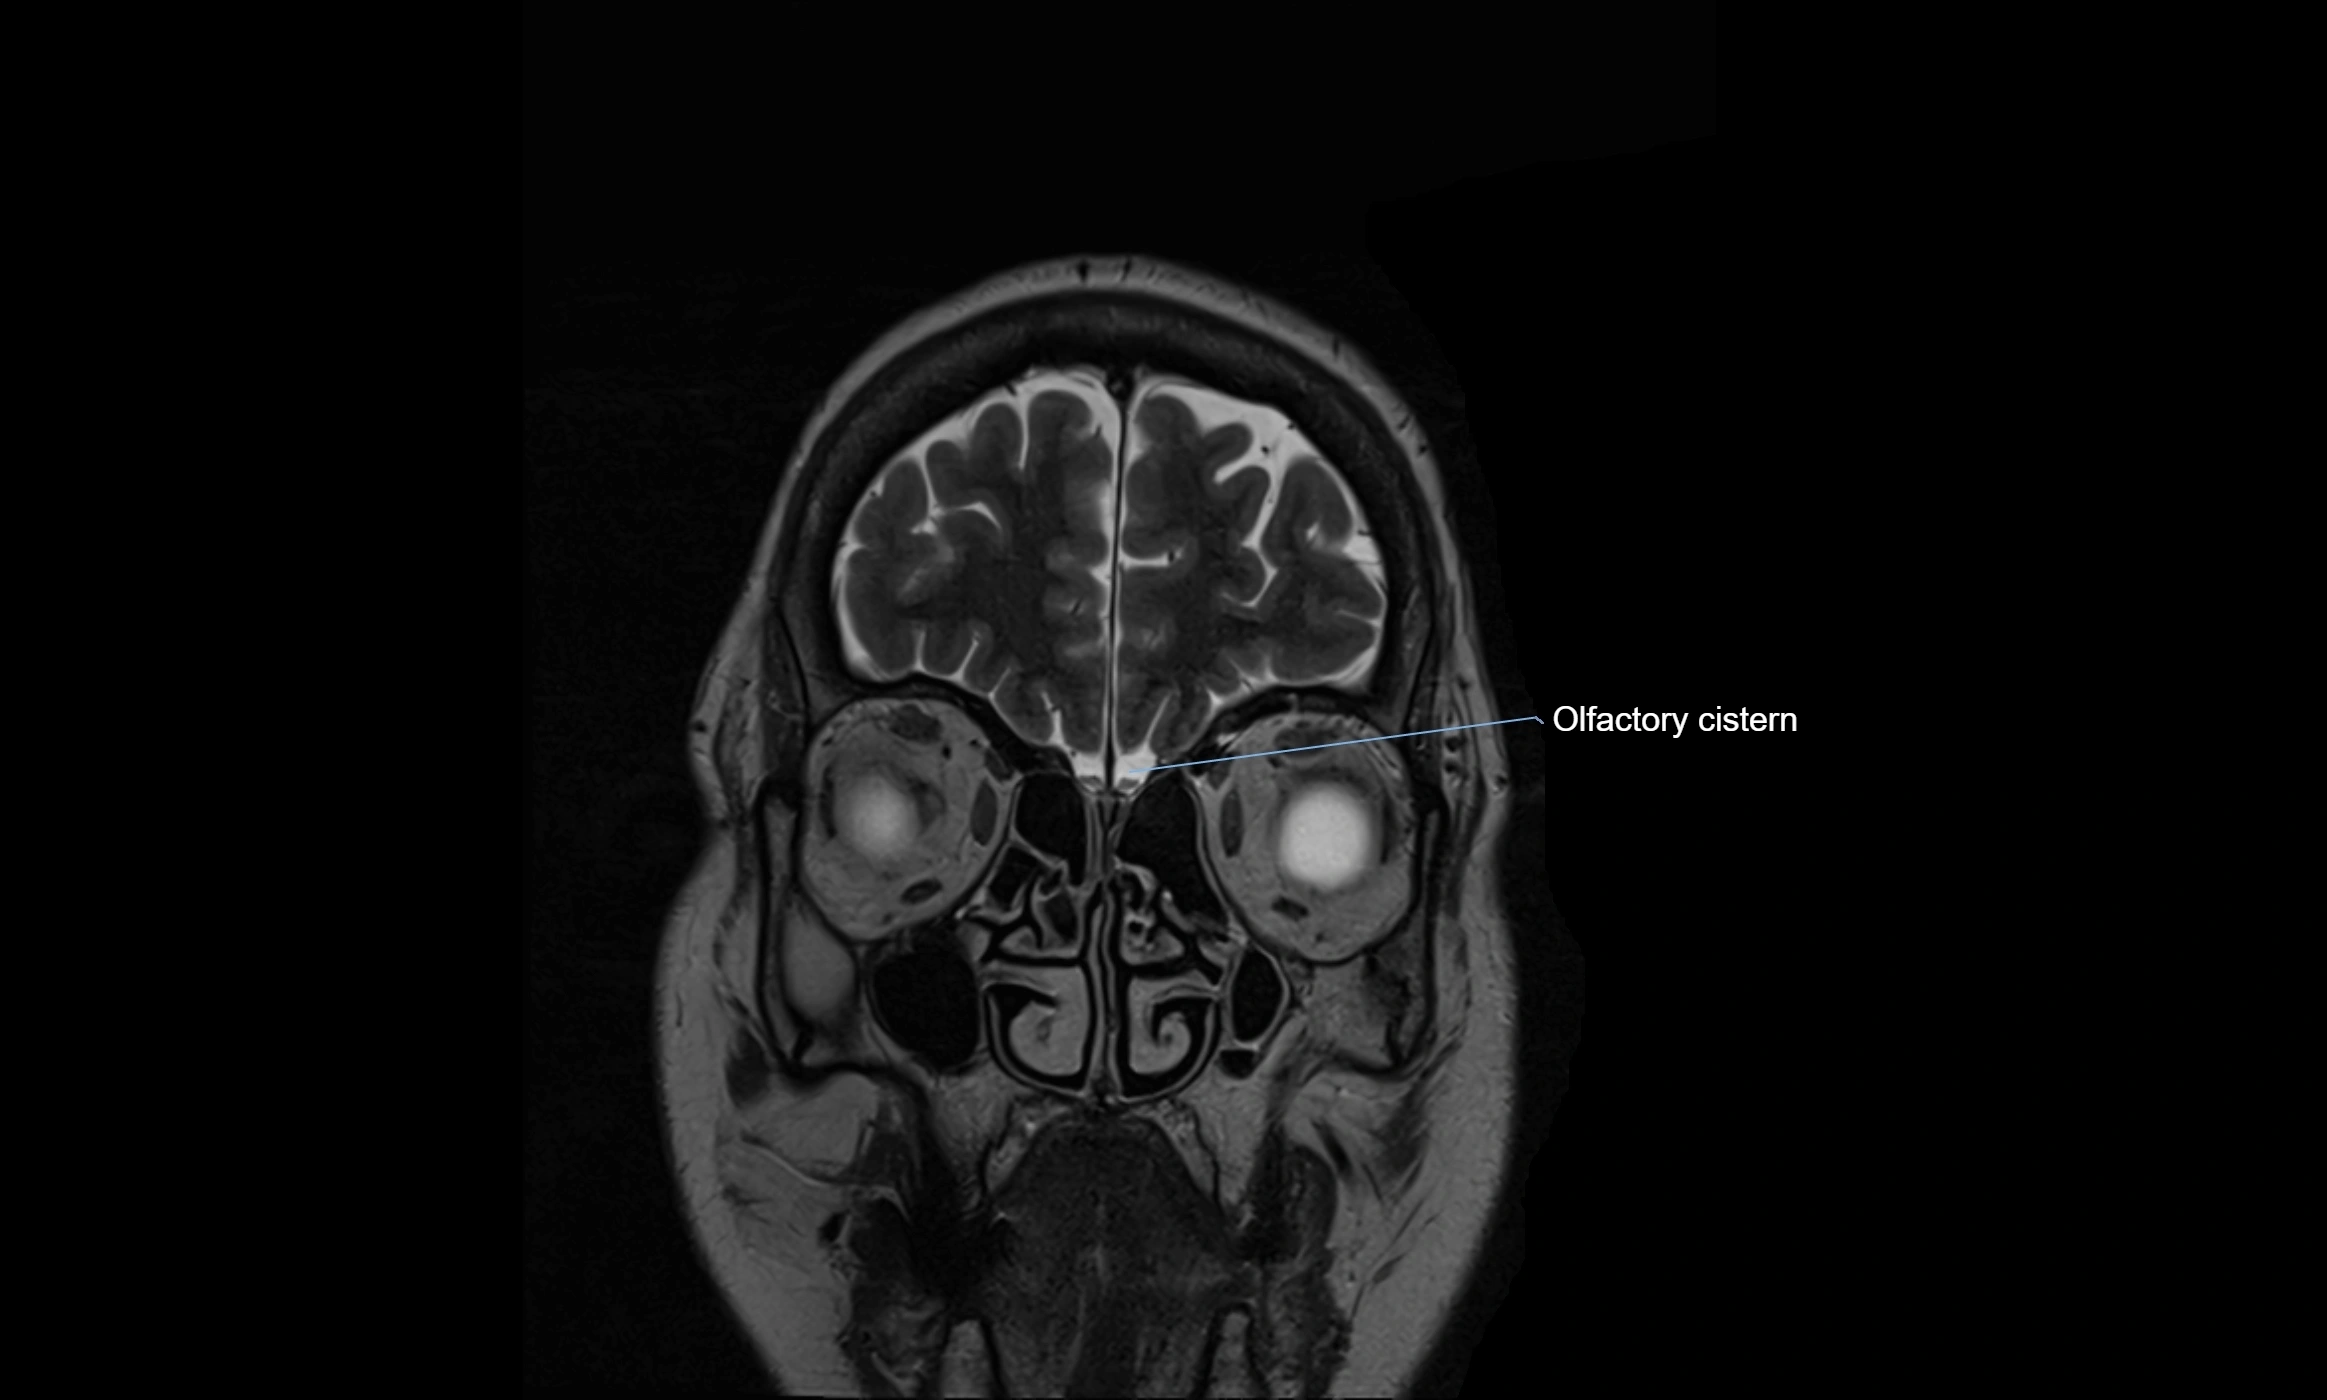

MRI images

image